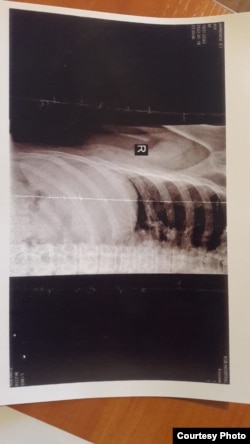

– Сол жерде соты болған, 10 тәулік әкімшілік жаза кескен. Ағамды ұрып-соғып, азаптап, он күнге қамаған. Зарлықты дене жарақатын түсіруге апармаған. Ол дәрігер шақыруды сұраған. Бірақ "өтірік айтасың" деп, медициналық көмек көрсетпеген. Қабырғасы мен тіс протезі сынған адамды он тәулік қамауда ұстаған. Қамаудан шыққан кезде ағамның денесіндегі жарақаттарын түсіріп алдық, – дейді Қалиасқар.